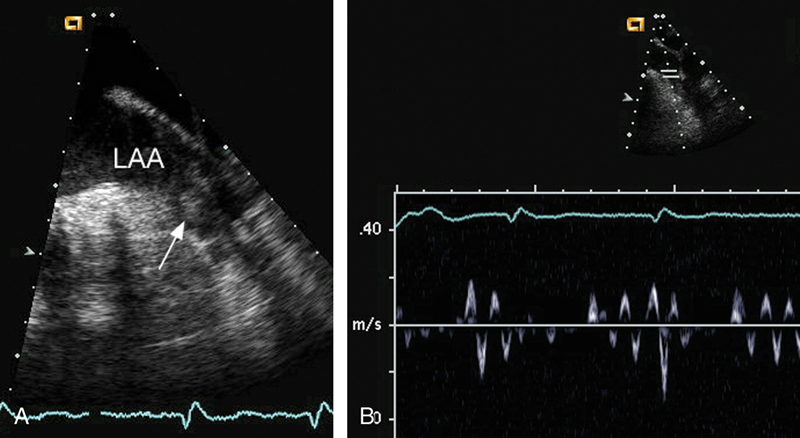

فحوصات تشخيصية لبعض امراض القلب والشرايين التاجية